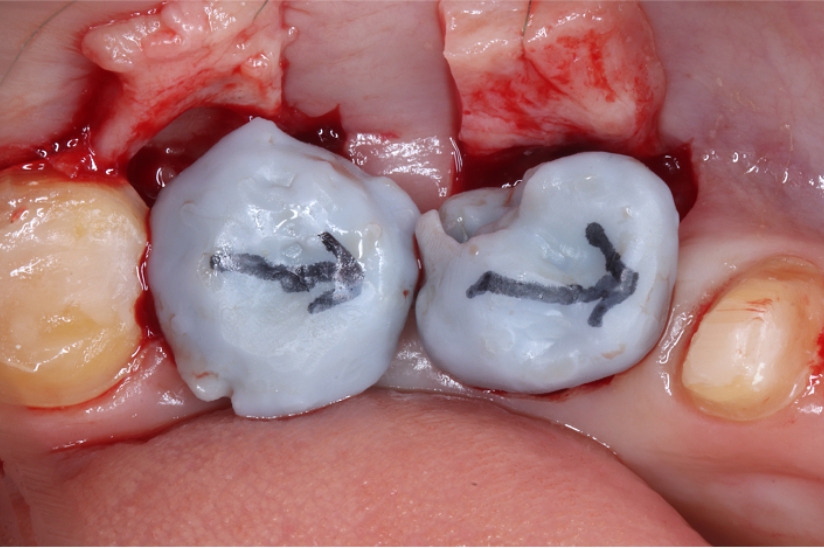

Under Treatment

主訴

インプラントはできないが、入れ歯もしたくない

治療内容

自家歯牙移植 / イニシャルトリートメント(大臼歯)レジンコア

治療期間

3ヶ月

治療費用

550,000

治療の

リスク

術後しばらくしてから骨性癒着、外部吸収を起こす可能性があります。